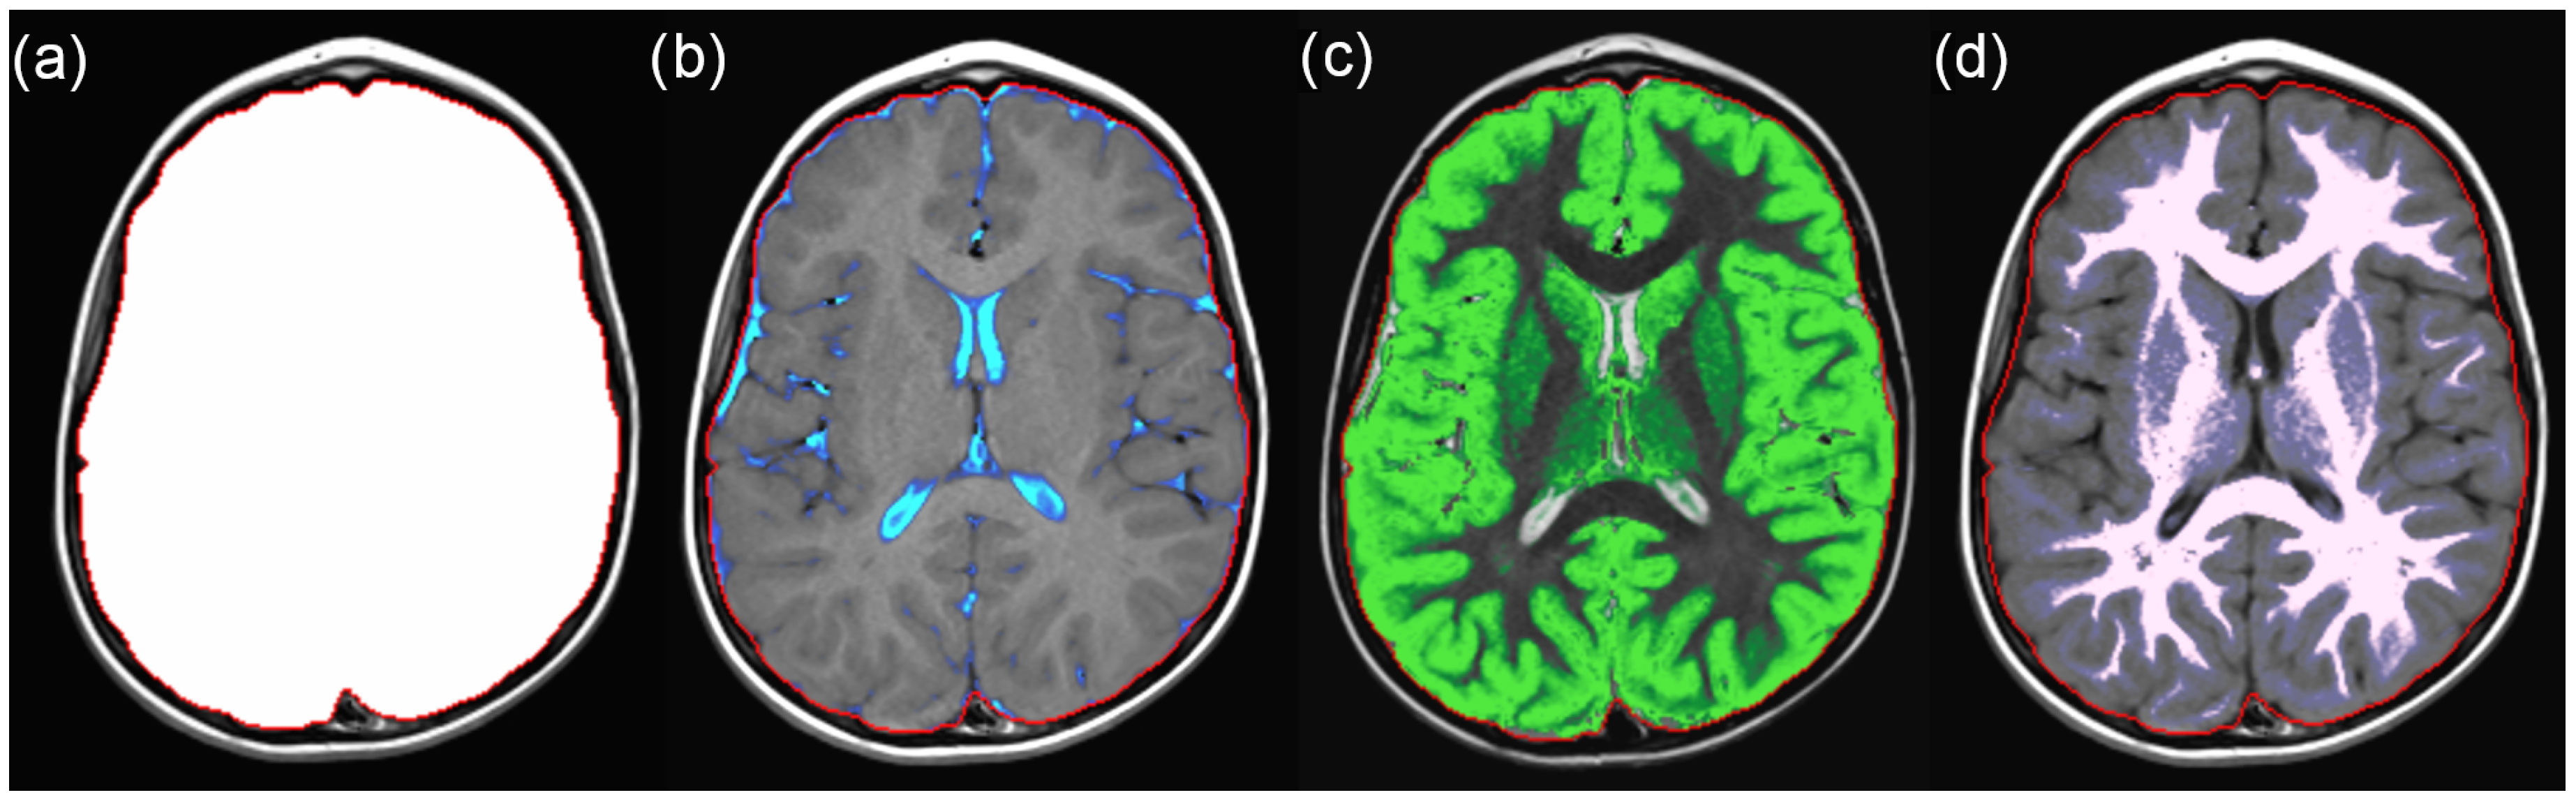

2.2. SyMRI Volume Measurements